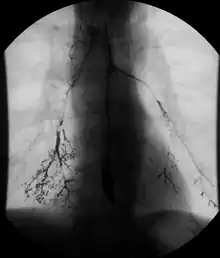

Barium follow-through showing the small bowel